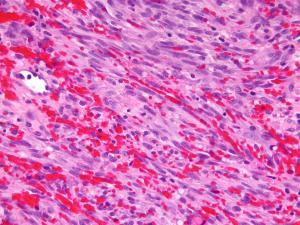

How viruses cause cancer and how viruses are being used to fight cancer.